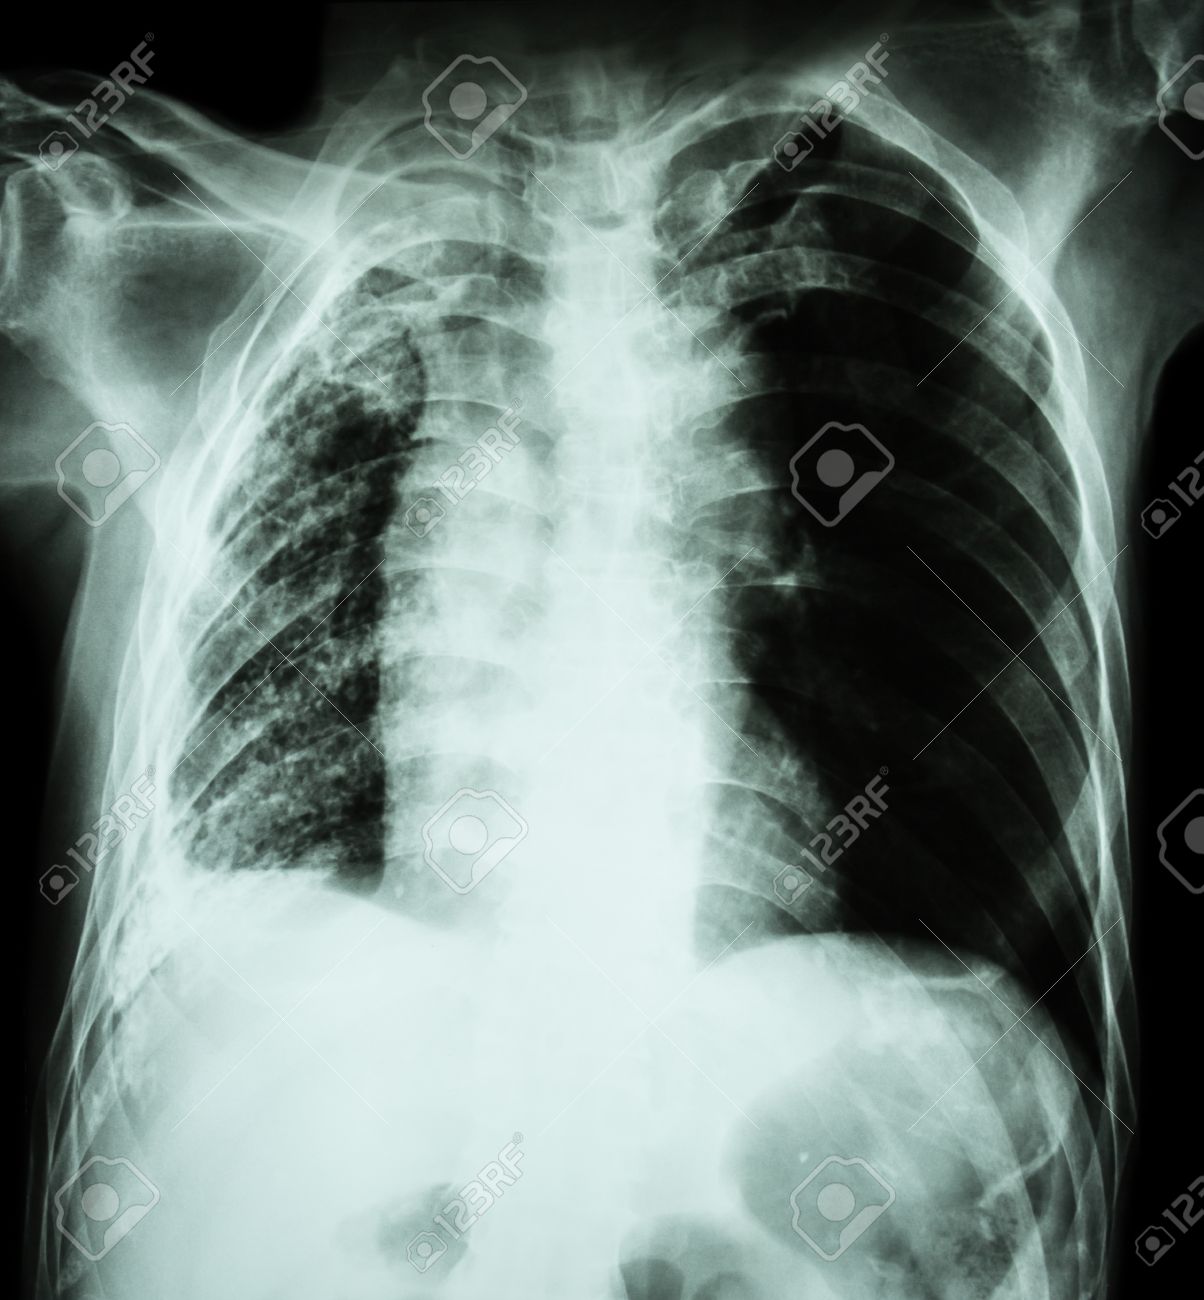

肺結核 胸部 X 線 無気肺と浸潤と結核菌感染による胸水 の写真素材 画像素材 Image